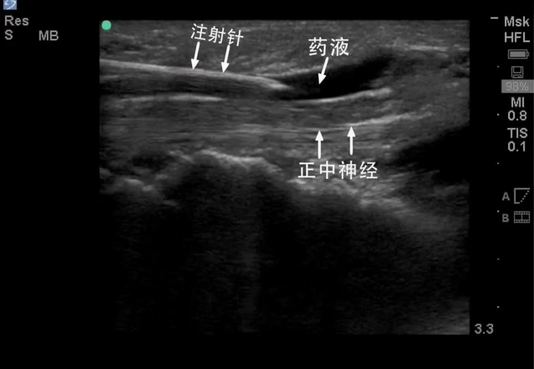

肌骨超声与疼痛医学的完美结合实现了实时,精准,可视化的操作,可减少药物剂量,提高治疗效果,迅速缓解病人痛苦,减少并发症的发生,从而达到精准医疗的目的。在肌骨超声的引导下进行慢性疼痛注射治疗,可实时显示靶目标针尖位置、进针路径中的重要结构,就像精确制导导弹一样,指哪打哪,显著增加了注射的准确性,同时又可避免对靶目标周围血管、神经的损伤,从而达到理想的治疗效果。

超声引导下注射示意图,图中可清晰显示注射针